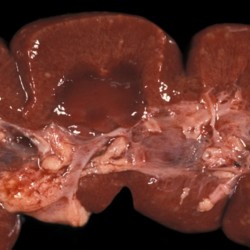

Etiquetes: N-91/88 2 total Bovine Specie: Bovine Organ: Kidney Lesion: Nephritis Lesion modifier: Nephritis - Purulent Disease: - Files/Expedient: N-91/88 Not viewed Bovine Specie: Bovine Organ: Kidney Lesion: Nephritis Lesion modifier: Nephritis - Purulent Disease: - Files/Expedient: N-91/88 Not viewed Títol Select...Avian (Exotic) (110)Avian (Poultry) (76)Bovine (317)Canine (935)Caprine (47)Equine (257)Feline (326)Ferret (19)General (127)Marine mammal (22)Non-human primate (20)Ovine (328)Porcine (379)Rabbit (61)Reptile (38)Rodent (28)Wildlife (91) Format Select...- (60)Abomasum (37)Adrenal gland (10)Blood (7)Blood vessel (50)Body as a whole (19)Bone (57)Bone marrow (21)Brain (93)Cloaca (1)Diaphragm (2)Ear (5)Esophagus (39)Eye (16)Fetus (12)Gallbladder (23)Gizzard (2)Heart (265)Intestine (356)Joint (32)Kidney (443)Larynx (5)Liver (326)Lung (264)Lymph node (91)Mammary gland (10)Mediastinum (1)Muscle (22)Nasal cavity (22)Nerve (7)Omasum (5)Oral cavity (63)Ovary (14)Oviduct (8)Pancreas (7)Parathyroid (5)Penis (10)Peritoneum (65)Pharynx (9)Pituitary gland (6)Placenta (7)Prostate (8)Proventriculus (3)Reticulum (1)Rumen (28)Sinus (7)Skin (181)Spinal cord (15)Spleen (105)Stomach (125)Teeth (1)Testicle (11)Thoracic cavity (31)Thymus (13)Thyroid gland (5)Tongue (32)Tonsils (11)Trachea (11)Urethra (5)Urinay bladder (61)Uterus (27)Vagina (1)Vulva (1)Yolk sac (1) Cobertura Select...- (152)Abomasitis (26)Abscess (27)Acidosis (1)Adenocarcinoma (20)Adenoma (9)Aerosacculitis (6)Agenesis (1)Agnathia (1)Alopecia (7)Amyloidosis (12)Aneurysm (6)Angiectasis (1)Anthracosis (1)Arteritis (11)Arthritis (15)Arthrogryposis (6)Artifact (4)Ascites (13)Atelectasis (8)Atherosclerosis (5)Atresia (1)Atrial septal defect (2)Atrophy (10)Autolysis (7)Bronchitis (6)Bronchopneumonia (26)Cachexia (2)Carcinoma (103)Cardiomyopathy (19)Cellulitis (2)Chemodectoma (4)Cholangiohepatitis (4)Cholangitis (19)Cholecystitis (4)Cholestasis (5)Chondrodysplasia (2)Chondrosarcoma (2)Chronic passive congestion (13)Chylothorax (2)Cirrhosis (6)Coelomitis (3)Coenurus cerebralis (4)Colitis (40)Congestion (17)Conjunctivitis (5)Coronitis (3)Cryptorchidism (3)Cyst (25)Cystitis (24)Dermatitis (69)Diaphragmatic hernia (4)Dilation (28)Discospondylitis (1)Disseminated intravascular coagulation (7)Dyschondroplasia (1)Dysplasia (29)Ectopia cordis (1)Ectopic ureter (1)Edema (55)Emphysema (5)Encephalitis (5)Endocardiosis (14)Endocarditis (26)Endometritis (5)Enteritis (118)Enterolith (6)Epulis (3)Esophagitis (14)Fasciitis (1)Fibrosis (7)Fibrous osteodystrophy (8)Fistula (1)Folliculitis (3)Fracture (2)Gastritis (34)Gingivitis (5)Glioma (8)Glomerulonephritis (21)Glossitis (25)Glycogenosis (1)Gout (8)Granuloma (2)Granulosa cell tumor (4)Hemangioma (9)Hemangiosarcoma (46)Hematoma (8)Hemoglobinuria (2)Hemopericardium (12)Hemoperitoneum (2)Hemorrhage (100)Hemosiderosis (7)Hemothorax (2)Hepatitis (78)Hernia (11)Histiocytosis (3)Hydatid cyst (11)Hydrocephalus (9)Hydrometra (1)Hydronephrosis (22)Hydropericardium (6)Hydrothorax (3)Hydroureter (5)Hyperkeratosis (8)Hyperostosis (4)Hyperplasia (37)Hypertrophy (9)Hypopigmentation (1)Hypoplasia (7)Hypopyon (1)Impaction (6)Infarction (63)Insulinoma (6)Intussusception (5)Jaundice (17)Laminitis (2)Laryngitis (2)Leiomyoma (5)Leukemia (13)Lipidosis (36)Lipoma (7)Lymphadenitis (45)Lymphadenopathy (7)Lymphangiectasia (6)Lymphangitis (5)Lymphoma (221)Malacia (11)Malignant melanoma (15)Mast cell tumor (11)Mastitis (8)Megaesophagus (2)Melanosis (3)Melena (4)Meningioma (6)Meningitis (6)Meningocele (2)Meningoencephalitis (5)Mesothelioma (5)Methemoglobinemia (2)Mineralization (10)Mucocele (5)Mucometra (1)Multilobular bone tumor (1)Mummification (3)Myelofibrosis (1)Myocarditis (4)Myositis (5)Necrosis (81)Nephritis (113)Nephroblastoma (6)Nephrosclerosis (1)Nephrosis (14)Neuritis (1)Obstruction (13)Omasitis (4)Omphalitis (1)Omphalophlebitis (7)Orchitis (4)Osteoarthrosis (5)Osteomyelitis (9)Otitis (2)Palatoschisis (3)Pancreatitis (3)Panniculitis (3)Papilloma (7)Parakeratosis (14)Patent ductus arteriosus (6)Peliosis hepatis (1)Perforation (17)Pericarditis (35)Peritonitis (39)Persistent right aortic arch (1)Pharyngitis (2)Pheochromocytoma (2)Phlebitis (2)Placentitis (6)Pleuritis (21)Pleuropneumonia (24)Pneumonia (109)Pneumothorax (3)Polycystosis (14)Polyp (5)Polyserositis (6)Posthitis (1)Proctitis (4)Prolapse (3)Prostatitis (3)Proventriculitis (1)Pyelonephritis (24)Pyometra (6)Pyothorax (4)Rhinitis (11)Rumenitis (6)Rupture (24)Salpingitis (3)Sarcoma (57)Sclerosis (1)Scoliosis (2)Seminoma (2)Sequestrum (2)Serous atrophy (14)Sinusitis (7)Splenitis (14)Splenomegaly (9)Spondylitis (6)Spondylosis (1)Stenosis (9)Stomatitis (32)Tenosynovitis (2)Teratoma (3)Thricobezoar (2)Thrombosis (16)Tonsilitis (4)Torsion (13)Tracheitis (4)Tympany (7)Typhlitis (8)Typhlocolitis (4)Ulcer (43)Urethritis (1)Urolithiasis (36)Uroperitoneum (1)Uveitis (1)Vasculitis (15)Ventricular septal defect (3)Volvulus (11) Matèria Select... - (14)- (1653)- (152)Abomasitis - Catarrhal (2)Abomasitis - Catarrhal-hemorrhagic (1)Abomasitis - Chronic (1)Abomasitis - Fibrinous-necrotizing (2)Abomasitis - Hyperplasic (5)Abomasitis - Hyperplasic - Chronic (1)Abomasitis - Necrotic (1)Abomasitis - Necrotizing (2)Abomasitis - Ulcerative (5)Adenocarcinoma (9)Aerosacculitis - Granulomatous (1)Amyloidosis - Chronic (1)Arteritis - Necrotic (2)Arteritis - Necrotizing (1)Arthritis - Chronic (4)Arthritis - Fibrinous-purulent (3)Arthritis - Serous (4)Arthritis - Subacute (1)Ascites - Serous (1)Atrophy - Serous (1)Bronchitis - Catarrhal (3)Bronchitis - Suppurative (1)Bronchopneumonia - Catarrhal-purulent (17)Bronchopneumonia - Fibrinous (1)Bronchopneumonia - Granulomatous (1)Bronchopneumonia - Purulent (1)Bronchopneumonia - Suppurative (5)Carcinoma - Adenocarcinoma (33)Carcinoma - Adenocarcinoma - Hepatocellular (2)Carcinoma - Adenocarcinoma - Mucinous (1)Carcinoma - Basosquamous (1)Carcinoma - Cholangiocellular (3)Carcinoma - Hepatocellular (4)Carcinoma - Metastatic (3)Carcinoma - Squamous cell carcinoma (13)Carcinoma - Transitional cell (2)Cardiomyopathy - Dilated (13)Cardiomyopathy - Hypertrophic (6)Cellulitis - Necrotizing (1)Cholangitis - Chronic (8)Cholangitis - Hyperplasic (3)Cholecystitis - Fibrinous-necrotizing (1)Coelomitis - Fibrinous (1)Coelomitis - Granulomatous (1)Colitis - Catarrhal (3)Colitis - Catarrhal-hemorrhagic (1)Colitis - Fibrinous (1)Colitis - Fibrinous-necrotizing (1)Colitis - Fibrinous-necrotizing (Diphtheritic) (6)Colitis - Granulomatous (2)Colitis - Hemorrhagic (4)Colitis - Hemorrhagic-necrotizing (3)Colitis - Necrotizing (2)Colitis - Ulcerative (6)Congestion - Chronic (2)Conjunctivitis - Hyperplasic (1)Conjunctivitis - Purulent (3)Coronitis - Ulcerative (1)Cystitis - Chronic (3)Cystitis - Fibrinous (1)Cystitis - Fibrinous-necrotizing (1)Cystitis - Follicular (1)Cystitis - Hemorrhagic (6)Cystitis - Hemorrhagic-ulcerative (1)Cystitis - Necrotizing (9)Cystitis - Perforated (1)Dermatitis - Granulomatous (14)Dermatitis - Hyperkeratotic (10)Dermatitis - Hyperplasic (proliferative) (1)Dermatitis - Hyperplastic (10)Dermatitis - Necrotizing (4)Dermatitis - Pustular (4)Dermatitis - Ulcerative (2)Dilation - Chronic (1)Discospondylitis - Necrotizing (1)Dysplasia - Follicular (5)Edema - Interstitial (6)Emphysema - Interstitial (1)Encephalitis - Granulomatous (1)Encephalitis - Nonsuppurative (1)Endocardiosis - Mitral (7)Endocardiosis - Mitral - Chronic (5)Endocarditis - Valvular (6)Endocarditis - Valvular - Mitral (7)Endocarditis - Valvular - Pulmonic (1)Endocarditis - Valvular - Subacute (1)Endocarditis - Valvular - Subaortic (5)Endocarditis - Valvular - Tricuspid (4)Endometritis - Purulent (3)Endometritis - Purulent-hemorrhagic (2)Enteritis - Catarrhal (23)Enteritis - Catarrhal - Acute (1)Enteritis - Catarrhal-hemorrhagic (5)Enteritis - Catarrhal-hemorrhagic - Acute (2)Enteritis - Fibrinous (16)Enteritis - Fibrinous - Acute (3)Enteritis - Fibrinous-necrotizing (7)Enteritis - Granulomatous (14)Enteritis - Granulomatous - Chronic (1)Enteritis - Granulomatous - Multifocal (1)Enteritis - Hemorrhagic (17)Enteritis - Hemorrhagic - Acute (1)Enteritis - Hemorrhagic-necrotizing (1)Enteritis - Hyperplasic (proliferative) (4)Enteritis - Necrotizing (4)Enteritis - Necrotizing - Acute (1)Enteritis - Necrotizing - Hemorrhagic (1)Enteritis - Necrotizing-ulcerative (2)Enteritis - Ulcerative (1)Enteritis - Ulcerative-hemorrhagic (1)Esophagitis - Erosive-ulcerative (6)Esophagitis - Necrotizing (4)Esophagitis - Ulcerative (1)Esophagitis - Ulcerative-necrotizing (1)Fasciitis - Fibrinous-purulent (1)Folliculitis - Purulent (2)Gastritis - Catarrhal (2)Gastritis - Chronic (1)Gastritis - Follicular (1)Gastritis - Hemorrhagic (2)Gastritis - Hemorrhagic-necrotizing (1)Gastritis - Hypertrophic (2)Gastritis - Inclusion bodies (1)Gastritis - Mineralization (1)Gastritis - Mycotic (1)Gastritis - Necrotizing (2)Gastritis - Ulcerative (6)Gastritis - Uremic (3)Gingivitis - Erosive (2)Gingivitis - Hyperplasic (proliferative) (1)Gingivitis - Necrotizing (1)Glomerulonephritis - Chronic (7)Glomerulonephritis - Membranoproliferative (3)Glomerulonephritis - Membranoproliferative - Chronic (1)Glomerulonephritis - Membranous (3)Glomerulonephritis - Membranous - Chronic (1)Glomerulonephritis - Proliferative (2)Glomerulonephritis - Subacute (1)Glossitis - Erosive (2)Glossitis - Granulomatous (6)Glossitis - Hyperplasic (1)Glossitis - Hyperplasic (proliferative) (2)Glossitis - Hyperplastic (1)Glossitis - Necrotizing (2)Glossitis - Necrotizing - Focal (1)Glossitis - Ulcerative (6)Glossitis - Ulcerative - Multifocal (1)Glossitis - Ulcerative - Subacute (1)Glycogenosis (1)Granuloma - Eosinophilic (1)Hemangiosarcoma - Metastatic (2)Hemorrhage - Acute (1)Hemorrhage - Subcapsular (3)Hepatitis - Abscess (9)Hepatitis - Acute (3)Hepatitis - Chronic (4)Hepatitis - Chronic interstitial (6)Hepatitis - Granulomatous (7)Hepatitis - Interstitial - Multifocal (1)Hepatitis - Interstitial - Subacute (1)Hepatitis - Necrotizing (17)Hepatitis - Necrotizing - Acute (2)Hepatitis - Necrotizing - Hemorrhagic (1)Hepatitis - Necrotizing - Subacute (1)Hepatitis - Pyogranulomatous (7)Hepatitis - Subacute (4)Hydronephrosis - Chronic (1)Hydropericardium - Chronic (1)Hyperplasia - Erythroid (1)Hyperplasia - Lymphoid (3)Hyperplasia - Myeloid (1)Hyperplasia - Nodular (8)Hypertrophy - Concentric (2)Hypertrophy - Eccentric (3)Infarction - Acute (17)Infarction - Acute - Multifocal (2)Infarction - Chronic (5)Infarction - Chronic - Multifocal (1)Infarction - Subacute (18)Infarction - Subacute - Focal (2)Laminitis - Chronic (2)Laryngitis - Necrotic (1)Laryngitis - Necrotizing (1)Leukemia - Lymphoid leukemia (2)Leukemia - Non-lymphoid leukemia (6)Lipidosis - Multifocal (1)Lipidosis - Panlobular (1)Lipidosis - Panlobular - Generalized (2)Lymphadenitis - Granulomatous (24)Lymphadenitis - Granulomatous - Chronic (3)Lymphadenitis - Hemorrhagic (1)Lymphadenitis - Necrotizing (5)Lymphadenitis - Necrotizing (caseous) (11)Lymphangitis - Granulomatous (1)Lymphangitis - Purulent (1)Lymphangitis - Ulcerative (1)Lymphoma - Alimentary lymphoma (7)Lymphoma - Cutaneous lymphoma (6)Lymphoma - Lymphosarcoma (2)Lymphoma - Mediastinal lymphoma (1)Lymphoma - Multicentric lymphoma (29)Malignant melanoma - Malignant (1)Malignant melanoma - Metastatic (1)Mast cell tumor - Metastatic (1)Mastitis - Fibrinous-purulent (2)Mastitis - Necrotic (1)Mastitis - Purulent (3)Mastitis - Suppurative (1)Meningitis - Fibrinous-purulent (2)Meningitis - Purulent (4)Meningoencephalitis - Necrotizing (3)Meningoencephalitis - Nonsuppurative (2)Mineralization - Metastatic (4)Myocarditis - Fibrous - Chronic (1)Myocarditis - Granulomatous (1)Myositis - Purulent (2)Necrosis - Acute (1)Necrosis - Cortical (5)Necrosis - Follicular (1)Necrosis - Papillary (8)Necrosis - Papillary - Acute (3)Necrosis - Subacute (3)Necrosis - Tubular (6)Nephritis - Embolic (2)Nephritis - Embolic suppurative (7)Nephritis - Granulomatous (27)Nephritis - Granulomatous - Chronic (1)Nephritis - Granulomatous - Multifocal (1)Nephritis - Interstitial (6)Nephritis - Interstitial - Acute (4)Nephritis - Interstitial - Chronic (41)Nephritis - Interstitial - Subacute (12)Nephritis - Purulent (7)Nephritis - Purulent - Acute (2)Nephritis - Purulent - Multifocal (3)Nephrosis - Cholemic (3)Nephrosis - Hemoglobinuric (10)Omasitis - Fibrinous-necrotizing (1)Omasitis - Hyperkeratotic (1)Omasitis - Necrotizing (2)Omphalophlebitis - Fibrinous-purulent (2)Omphalophlebitis - Purulent (3)Orchitis - Necrotizing (1)Osteomyelitis - Necrotizing (7)Osteomyelitis - Purulent (2)Otitis - Necrotizing (1)Otitis - Proliferative (1)Pancreatitis - Acute (1)Pancreatitis - Chronic (1)Pancreatitis - Granulomatous (1)Panniculitis - Fibrinous-purulent (1)Panniculitis - Necrotic (1)Panniculitis - Parasitic (1)Perforation - Acute (2)Pericarditis - Fibrinous (19)Pericarditis - Fibrinous - Subacute (1)Pericarditis - Fibrinous-necrotizing (1)Pericarditis - Fibrinous-purulent (3)Pericarditis - Fibrous (1)Pericarditis - Fibrous - Chronic (1)Pericarditis - Gangrenous (6)Pericarditis - Granulomatous (1)Pericarditis - Granulomatous - Chronic (2)Peritonitis - Acute (1)Peritonitis - Fibrinous (11)Peritonitis - Fibrinous - Subacute (1)Peritonitis - Fibrinous-purulent (5)Peritonitis - Fibrous (3)Peritonitis - Granulomatous (6)Peritonitis - Purulent (1)Peritonitis - Purulent-hemorrhagic (1)Peritonitis - Pyogranulomatous (3)Pharyngitis - Fibrinous-necrotizing (1)Pharyngitis - Ulcerative (1)Pheochromocytoma - Metastatic (1)Phlebitis - Purulent (1)Placentitis - Fibrinous-necrotizing (1)Placentitis - Necrotic (1)Placentitis - Necrotizing (1)Pleuritis - Chronic (1)Pleuritis - Fibrinous (3)Pleuritis - Fibrinous-purulent (2)Pleuritis - Fibrous (2)Pleuritis - Granulomatous (3)Pleuritis - Hyperplastic (2)Pleuritis - Purulent (2)Pleuritis - Pyogranulomatous (1)Pleuropneumonia - Fibrinous (13)Pleuropneumonia - Fibrinous-necrotizing (5)Pleuropneumonia - Granulomatous (2)Pleuropneumonia - Hemorrhagic-necrotizing (4)Pneumonia - Aspiration (11)Pneumonia - Bronchointerstitial (4)Pneumonia - Bronchointerstitial - Subacute (1)Pneumonia - Embolic (5)Pneumonia - Granulomatous (37)Pneumonia - Granulomatous - Multifocal (4)Pneumonia - Hemorrhagic-necrotizing (2)Pneumonia - Interstitial (7)Pneumonia - Interstitial - Acute (8)Pneumonia - Interstitial - Chronic (6)Pneumonia - Interstitial - Subacute (15)Pneumonia - Necrotizing (2)Pneumonia - Pyogranulomatous (2)Pneumonia - Verminous (5)Polyserositis - Fibrinous (6)Polyserositis - Fibrous (1)Proctitis - Fibrinous-necrotizing (1)Proctitis - Parasitic (2)Prostatitis - Purulent (1)Pyelonephritis - Acute (2)Pyelonephritis - Chronic (3)Rhinitis - Catarrhal (2)Rhinitis - Fibrinous (1)Rhinitis - Granulomatous (4)Rhinitis - Purulent (3)Rumenitis - Acute (1)Rumenitis - Erosive (1)Rumenitis - Necrotizing (1)Rupture - Acute (3)Sarcoma - Fibrosarcoma (12)Sarcoma - Hemangiosarcoma (11)Sarcoma - Histiocytic (7)Sarcoma - Metastatic (1)Sarcoma - Multilobular tumor of bone (1)Sequestrum - Chronic (2)Sinusitis - Suppurative (1)Splenitis - Granulomatous (8)Splenitis - Granulomatous - Chronic (1)Splenitis - Necrotizing (3)Splenitis - Necrotizing (caseous) (2)Spondylitis - Necrotizing (2)Stenosis - Intestinal (1)Stenosis - Valvular - Subaortic (4)Stomatitis - Erosive (12)Stomatitis - Erosive-ulcerative (3)Stomatitis - Fibrinous-necrotizing (1)Stomatitis - Fibrinous-necrotizing (Diphtheritic) (1)Stomatitis - Granulomatous (1)Stomatitis - Hyperplasic (1)Stomatitis - Hyperplasic (proliferative) (1)Stomatitis - Necrotizing (2)Stomatitis - Ulcerative (5)Stomatitis - Ulcerative - Multifocal (1)Stomatitis - Ulcerative-necrotizing (1)Tonsilitis - Necrotizing (4)Torsion - Acute passive hyperemia (5)Tracheitis - Catarrhal (3)Tracheitis - Fibrinous (1)Tracheitis - Granulomatous (1)Typhlitis - Catarrhal (1)Typhlitis - Fibrinous-necrotizing (2)Typhlitis - Hemorrhagic (2)Typhlitis - Ulcerative-hemorrhagic (1)Typhlocolitis - Fibrinous-necrotizing (2)Typhlocolitis - Proliferative (1)Ulcer - Chronic (6)Ulcer - Multifocal (2)Ulcer - Mycotic (1)Ulcer - Perforated (6)Urethritis - Hemorrhagic (1)Urolithiasis - Chronic (2)Uveitis - Granulomatous (1)Vasculitis - Granulomatous (1)Vasculitis - Necrotizing (1) Editor Select...- (1970)Acidosis (2)Actinobacillosis (Pleuropneumonia) (11)Aelurostrongylosis (2)African horse sickness (13)African swine fever (14)Alopecia X (1)Anaplasmosis (4)Anthrax (2)Aortic thromboembolism (feline) (7)Ascariasis (15)Aspergillosis (18)Atopic dermatitis (1)Atrophic rhinitis (3)Babesiosis (6)Blackhead (1)Bluetongue (11)Border disease (2)Bovine viral diarrhea (21)Brucellosis (2)Candidiasis (5)Canine distemper (14)Caprine arthritis-encephalitis (2)Capture myopathy (1)Cardiac insufficiency (17)Caseous lymphadenitis (7)Chlamydiosis (2)Classical swine fever (19)Clostridiosis (19)Coccidiosis (9)Coenurosis (4)Colibacillosis (21)Contagious ecthyma (7)Copper toxicosis (11)Cowdriosis (Heartwater) (3)Cryptococcosis (3)Cryptosporidiosis (2)Cysticercosis (23)Demodicosis (1)Diabetes (1)Dicrocoeliosis (5)Dictyocaulosis (4)Dirofilariasis (7)Discoid lupus erythematosus (3)Echinococcosis (17)Edema disease (7)Egg drop syndrome (1)Encephalitozoonosis (5)Enterotoxemia (1)Enzootic bovine leukosis (46)Epitheliogenesis imperfecta (3)Equine rhinopneumonitis (2)Equine verminous arteritis (strongylosis) (7)Erysipelas (5)Exudative epidermitis (7)Fasciolasis (11)Feline eosinophilic dermatoses (1)Feline hepatic lipidosis (8)Feline histiocytosis (4)Feline infectious peritonitis (38)Feline leukemia (4)Feline lower urinary tract disease (3)Feline panleukopenia (16)Feline viral rhinotracheitis (1)Flea allergy dermatitis (1)Foot and mouth disease (2)Gasterophilosis (4)Glasser's disease (15)Gousiekte (4)Gout (6)Haemonchosis (9)Hemolytic anemia (4)Hemorrhagic diathesis (1)Hepatic insufficiency (11)Hepatosis dietetica (7)Herpesvirosis (6)Hyperadrenocorticism (7)Hyperparathyroidism (10)Hypertrophic osteopathy (6)Hypervitaminosis D (1)Hypodermosis (1)Inclusion body hepatitis (4)Infectious bovine rhinotracheitis (5)Infectious bronchitis (5)Infectious canine hepatitis (13)Influenza (4)Juvenile nephropathy (8)Lamb dysentery (4)Leishmaniasis (28)Leptospirosis (1)Leukosis (5)Listeriosis (4)Lumpy skin disease (3)Maedi-visna (4)Malignant catarrhal fever (12)Mange (6)Mannheimiosis (5)Marek's disease (7)Metabolic bone disease (2)Mucoid enteropathy (5)Mulberry heart disease (5)Myasis (1)Mycobacteriosis (22)Mycosis fungoides (6)Myxomatosis (3)Necrobacillosis (5)Neonatal isoerythrolysis (6)Nocardiosis (4)Oestrosis (2)Onchocerciasis (1)Osteochondrosis (1)Ostertagiosis (6)Ovine pulmonary adenocarcinoma (5)Oxyuriasis (1)Pacheco's disease (4)Papillomatosis (6)Paratuberculosis (18)Parvovirosis (17)Pasteurellosis (11)Pemphigus foliaceus (1)Periodontal disease (1)Polioencephalomalacia of ruminants (4)Polyarteritis nodosa (3)Polycystic kidney disease (13)Porcine circovirosis (11)Porcine dermatitis and nephropathy syndrome (9)Porcine proliferative enteropathy (4)Porcine reproductive and respiratory syndrome (6)Porcine stress syndrome (1)Pox (13)Pregnancy toxemia (3)Proventricular dilatation disease (2)Pseudotuberculosis (yersiniosis) (2)Psittacine beak and feather disease (PBFD) (5)Pyoderma (4)Q fever (4)Rabbit hemorrhagic disease (2)Renal insufficiency (12)Reticuloendotheliosis (2)Rhodococcosis (1)Rickets (1)Rinderpest (2)Salmonellosis (34)Sarcosporidiosis (2)Schmallenberg (7)Septicemia (23)Spirocercosis (11)Streptococcosis (5)Strongylosis (1)Swine dysentery (5)Systemic coronavirosis (5)Tetralogy of Fallot (5)Theileriosis (13)Thromboembolism (5)Toxoplasmosis (11)Transmissible viral proventriculitis (1)Traumatic reticuloperitonitis (3)Traumatism (16)Tuberculosis (58)Ulcerative lymphangitis (1)Uremic syndrome (20)Viral arthritis (6)White muscle disease (9)Wobbler syndrome (2)Xanthomatosis (1)Zygomycosis (4) Idioma Select...- (1180)Bacterial (501)Degeneration (106)Fungal (46)Hemodynamic (112)Idiopathic (22)Inflammation (58)Malformation (88)Neoplasia (343)Nutritional (41)Parasitic (243)Physical/Chemical (93)Toxic (44)Viral (304) Ítem destacat Canine Puppy. Corneal edema